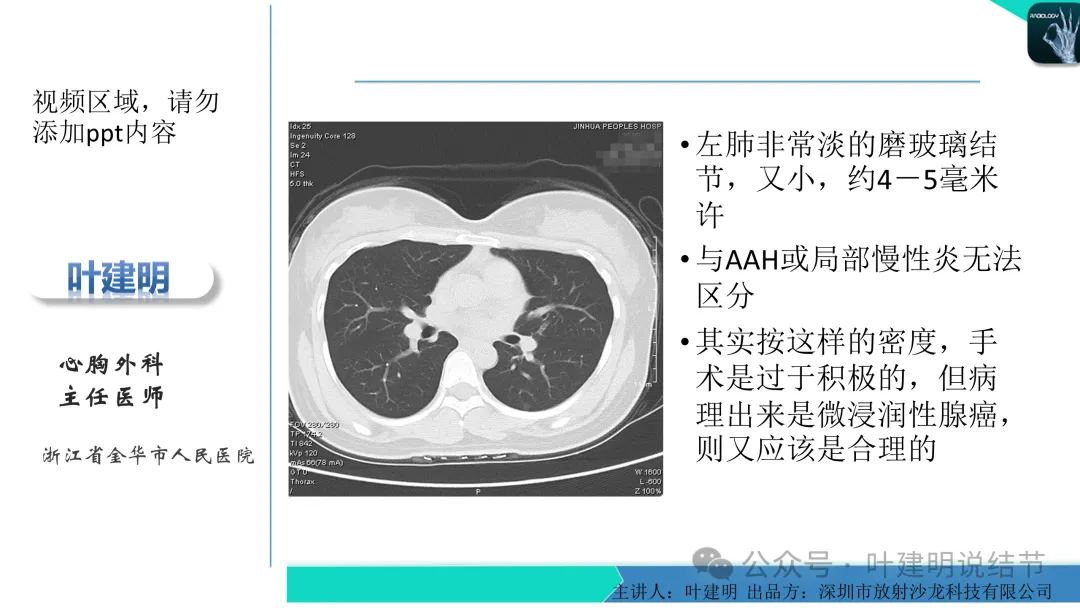

左下叶结节,轮廓稍显模糊,邻近有血管走行,无血管弯征,病灶中间密度稍低,结节密度很淡,仅小片状模糊影似的。

右上叶与左下叶这两处结节均密度很低,非常淡,而且瘤肺边界并不是特别清晰,考虑少许肺泡上皮增生可能性大,目前没有什么风险,可常规年度复查随访。不能太着急,也不必太着急干预处理。我一直强调不要管最后病理是什么,而是从影像上判断风险如何、纯不纯,密度高不高,还能不能观察。你这种不单密度低,还小,不需要过分担心的,安心随访便可。意见供参考!

当地说考虑微浸润性腺癌的左下主病灶影像连续层面展示:

病灶出现,显模糊。

上图层面轮廓较清,但密度很淡,似见血管走行,但靠左前方的似条状磨玻璃密度与血管连着的到底是血管分支还是结节的一部分,其实并不确切。如果其实是血管分支,那病灶与它之间就不是空泡。

病灶在此层整体边缘显糊,灶内有空泡似的,瘤肺边界欠清。

边缘不平,还是灶内多发小空泡?邻近血管与之紧贴,但血管无异常走行。病灶密度很低,显糊。

中间所谓空泡更像是细支气管扩张,内壁非常光滑且圆形。

病灶边缘区淡而模糊。

这个病灶会是微浸润性腺癌吗?当然没有病理诊断,我也不能说百分之百必不会,但这样的病灶已经风险大到必得尽快手术切除干预了吗?显然还早着呢:1、影像不是典型的结节状;2、边缘与轮廓模糊不清;3、灶内似有细支气管扩张(更容易是细支气管扩张伴少许周围炎或肺泡上皮增生);4、血管邻近走但无牵拉影响;5、没有实性成分,没有锐利毛刺,没有胸膜牵拉,没有血管进入,没有任何倾向风险性高的影像特点。我一直强调:肺结节是否要干预处理,不要纠结于最后病理是什么,而要看风险高低;而风险高低的最重要术前判断依据一是随访有无进展,二是有没有实性成分。只要没有肉眼可见的影像上的实性成分,风险就是低的!何况病理也是人看的,原位还是微浸润,不典型增生还是原位有时也在一念之间。